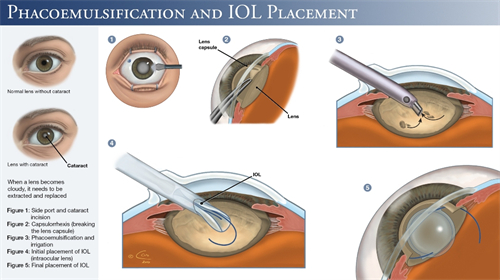

白内障手术是一种非常常见且安心的眼科手术,通常采用超声乳化技术将模糊的晶状体取出,然后植入人工晶状体以改善眼部视力。